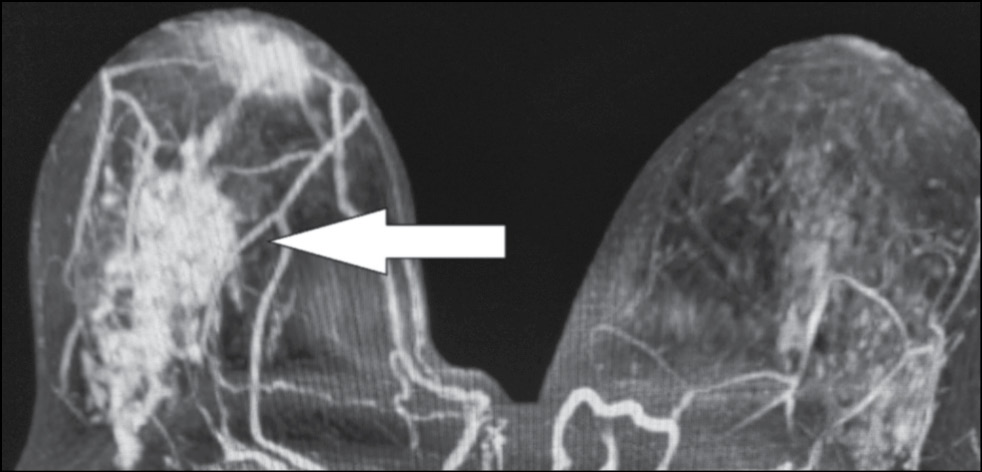

A 59-year-old patient complained of erosive changes in the nipple (Fig. 1). Physical examination revealed erythema, erosion, and nipple retraction. Doppler ultrasonography with color flow mapping revealed increased blood flow in the nipple projection (Fig. 2). Mammography findings were normal. To assess the extent of disease spread, breast MRI with contrast enhancement was performed. The early postcontrast series (Fig. 3) and maximum intensity projection (MIP) images (Fig. 4) showed a segmental contrast retroareolar area from the nipple level to posterior breast sections. Ultrasound-guided core biopsy followed by immunohistochemical analysis revealed Paget’s disease of the nipple with high-grade intraductal carcinoma in situ. Receptors for estrogen (G3 ER) and progesterone (PR) were negative. Oncogenic protein Ki-67 was 45%.

Figure 3. Magnetic resonance imaging of Paget’s disease (early enhancement phase): the retroareolar area of segmental enhancement from the nipple level to the posterior breast (arrow).